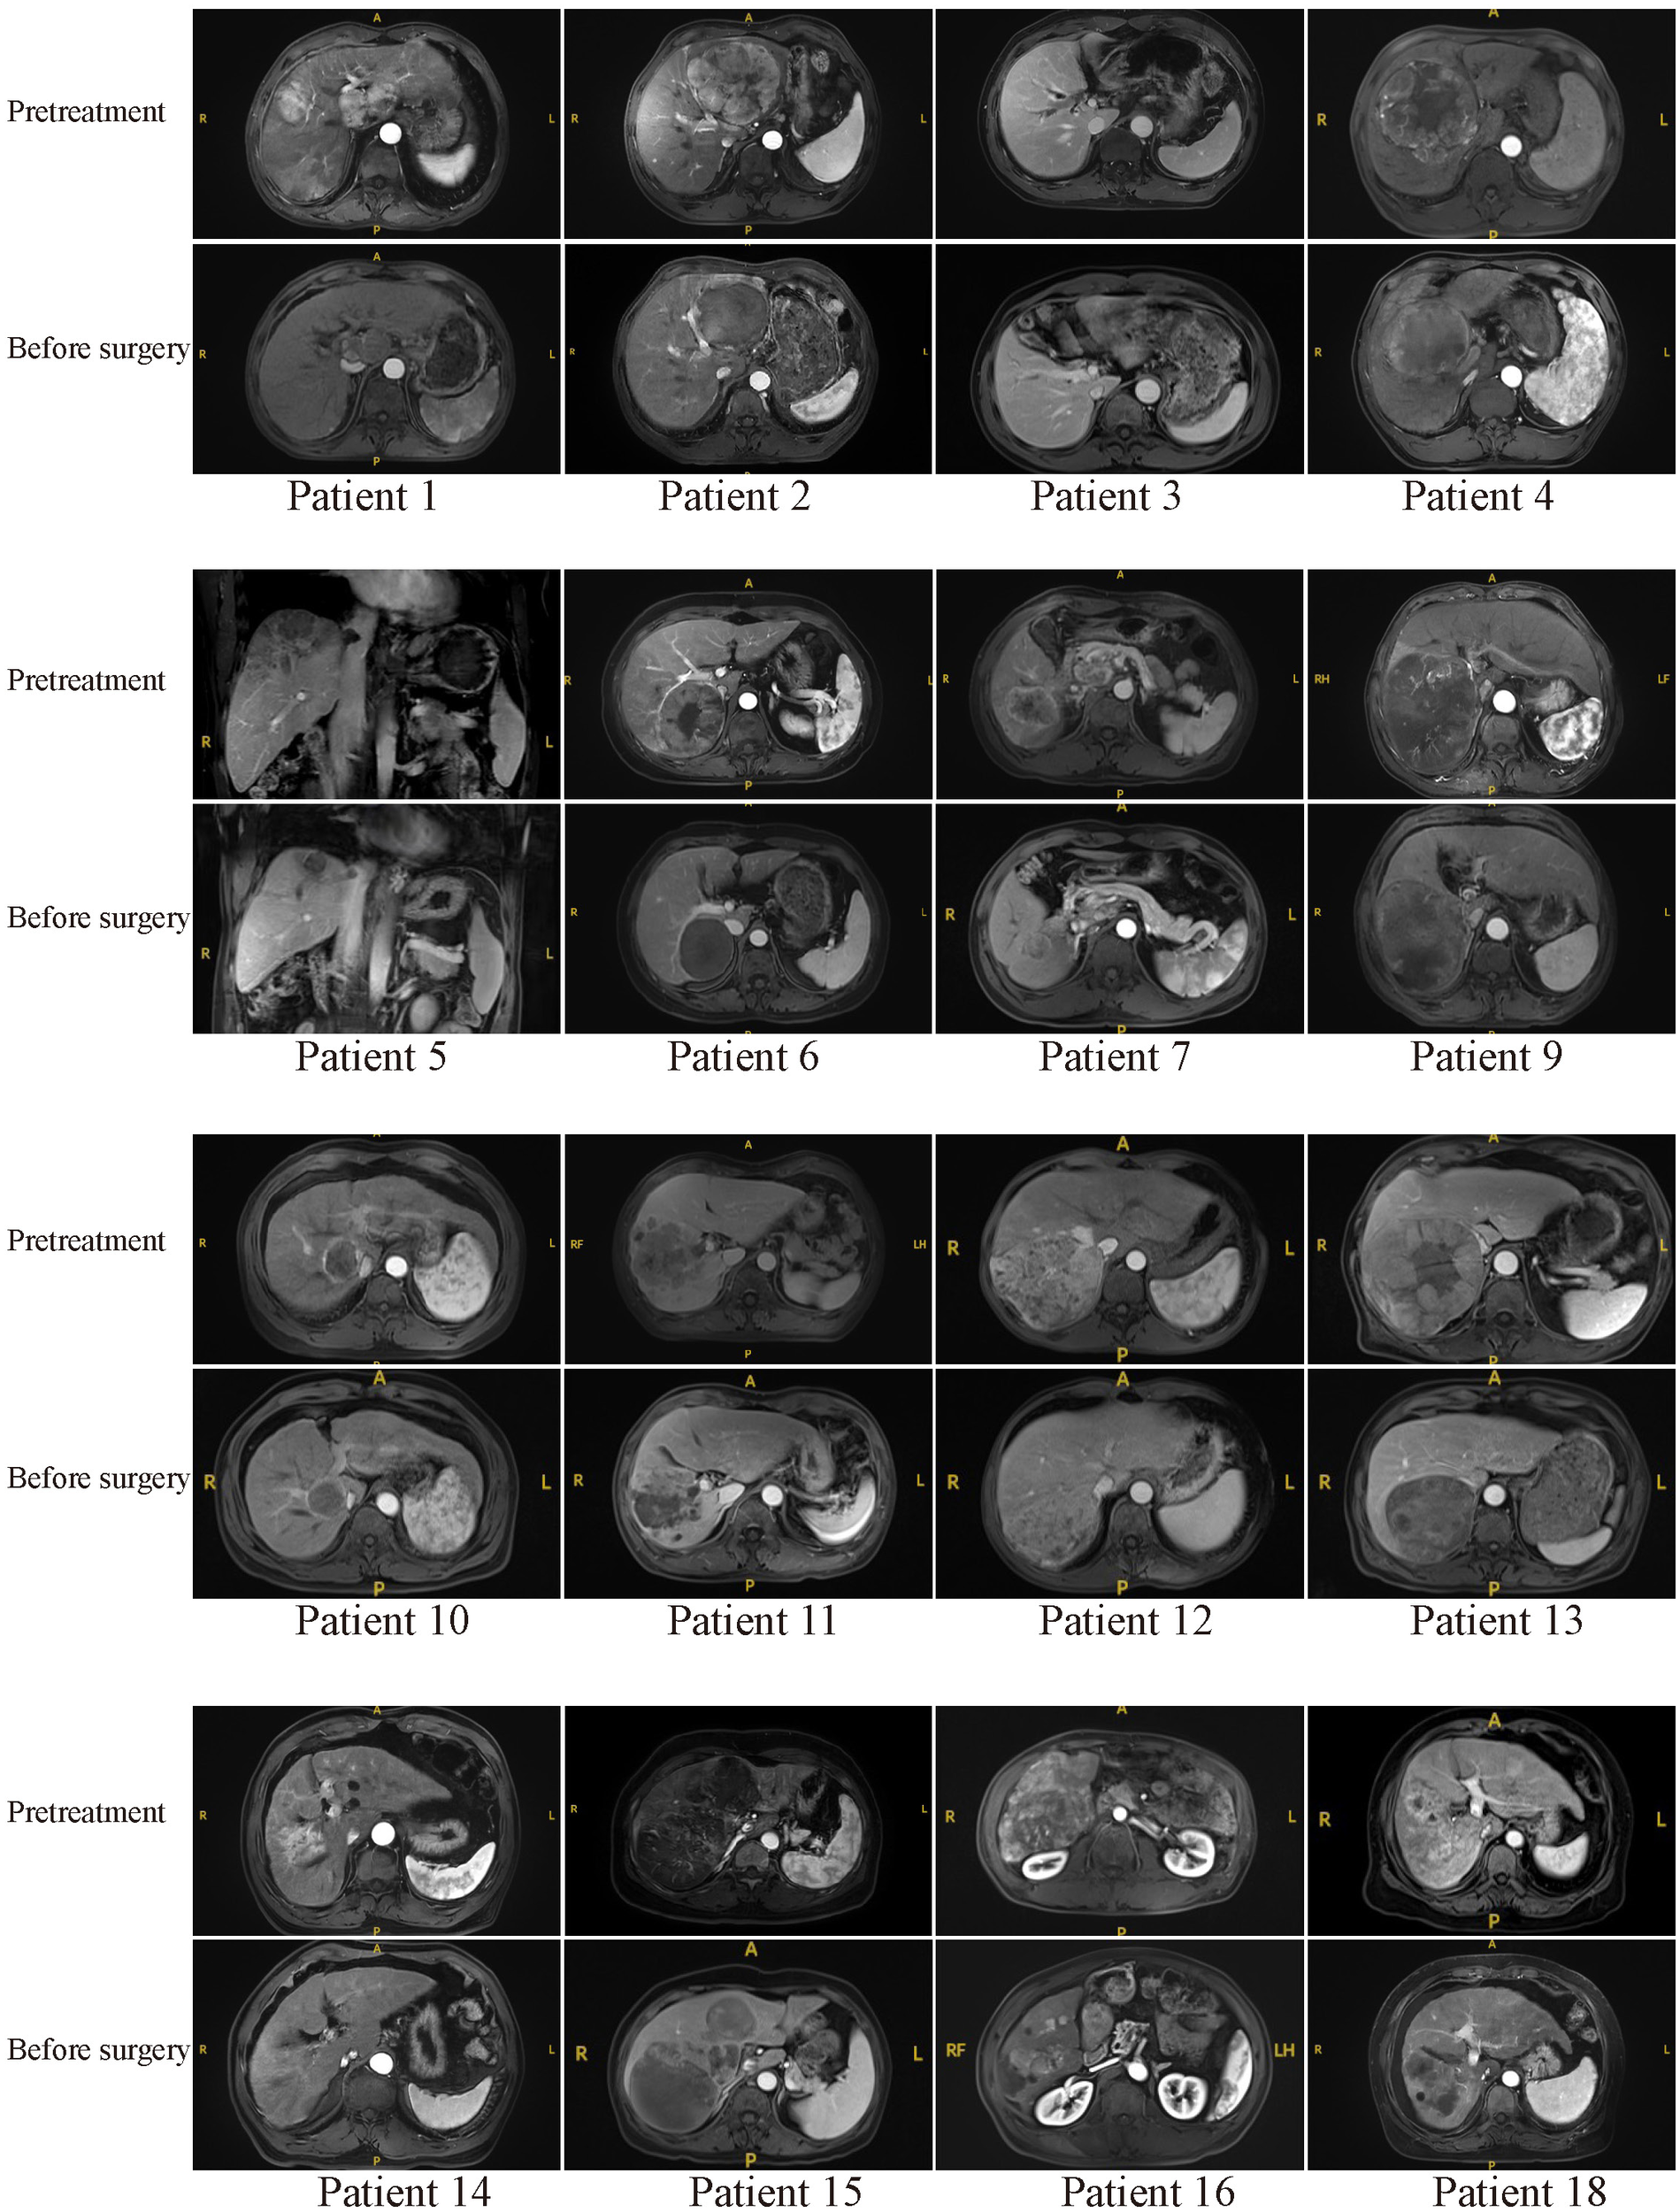

Typical MR or CT imaging scans of other patients (besides patients 8 and 17) before systemic treatment and before surgery were also listed in Figures 4, 5. The major reason for unresectability were tumor invasion into major portal vein (patients 12, 18 and 22) and the main branches of the portal vein (patients 2, 7, 9, 11, 14, 20, 24, 25, 26, 27 and 28), into hepatic vein or inferior vena cava (patients 5, 21, 29 and 30), into right hepatic bile duct (patient 3), multiple intrahepatic lesions (patients 1, 6, 15, 16, 19 and 23), insufficient remnant liver volume (patients 4 and 13), anatomical constraints for curative resection (patient 10), concomitant hilar or retroperitoneal lymph node metastasis (patients 7, 20 and 21). Obvious tumor regression was observed in all these cases before surgery.

Figure 4

Pretreatment and preoperative MR scans of patients 1-18 (except patients 8 and 17).